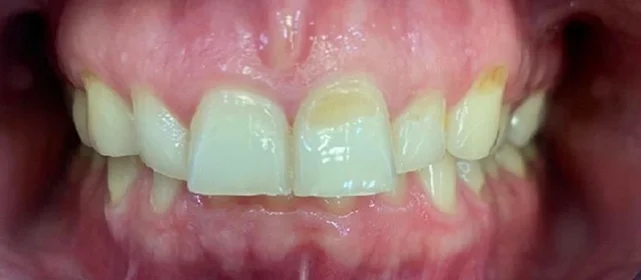

Верхняя челюсть выступала вперёд относительно нижней с обеих сторон (II класс по Энглю). Обе челюсти сужены, зубы стояли скученно. Нарушена кривая смыкания — жевательные зубы были на разной высоте. На двух передних зубах верхней челюсти ранее установлены металлокерамические коронки.

Проблема: Пациентку беспокоили неровные зубы и неправильный прикус. При осмотре нашли сразу несколько проблем: обе челюсти сужены, зубы стоят скученно, верхняя челюсть выступает вперёд (II класс по Энглю), кривая смыкания деформирована — жевательные зубы на разной высоте. На двух передних зубах верхней челюсти стояли старые металлокерамические коронки, которые нужно было учитывать при планировании.

Непростой случай: II класс, сужение, скученность, деформация кривой Шпее и металлокерамические коронки на 11 и 21. Коронки ограничивают варианты ретенции — на верхней челюсти вместо ретейнера используем капы. Это осознанное решение, принятое совместно с пациенткой. 64 капы за 20 месяцев — хороший темп для такого объёма. Основной набор сделал базу, дозаказы довели до нормы.